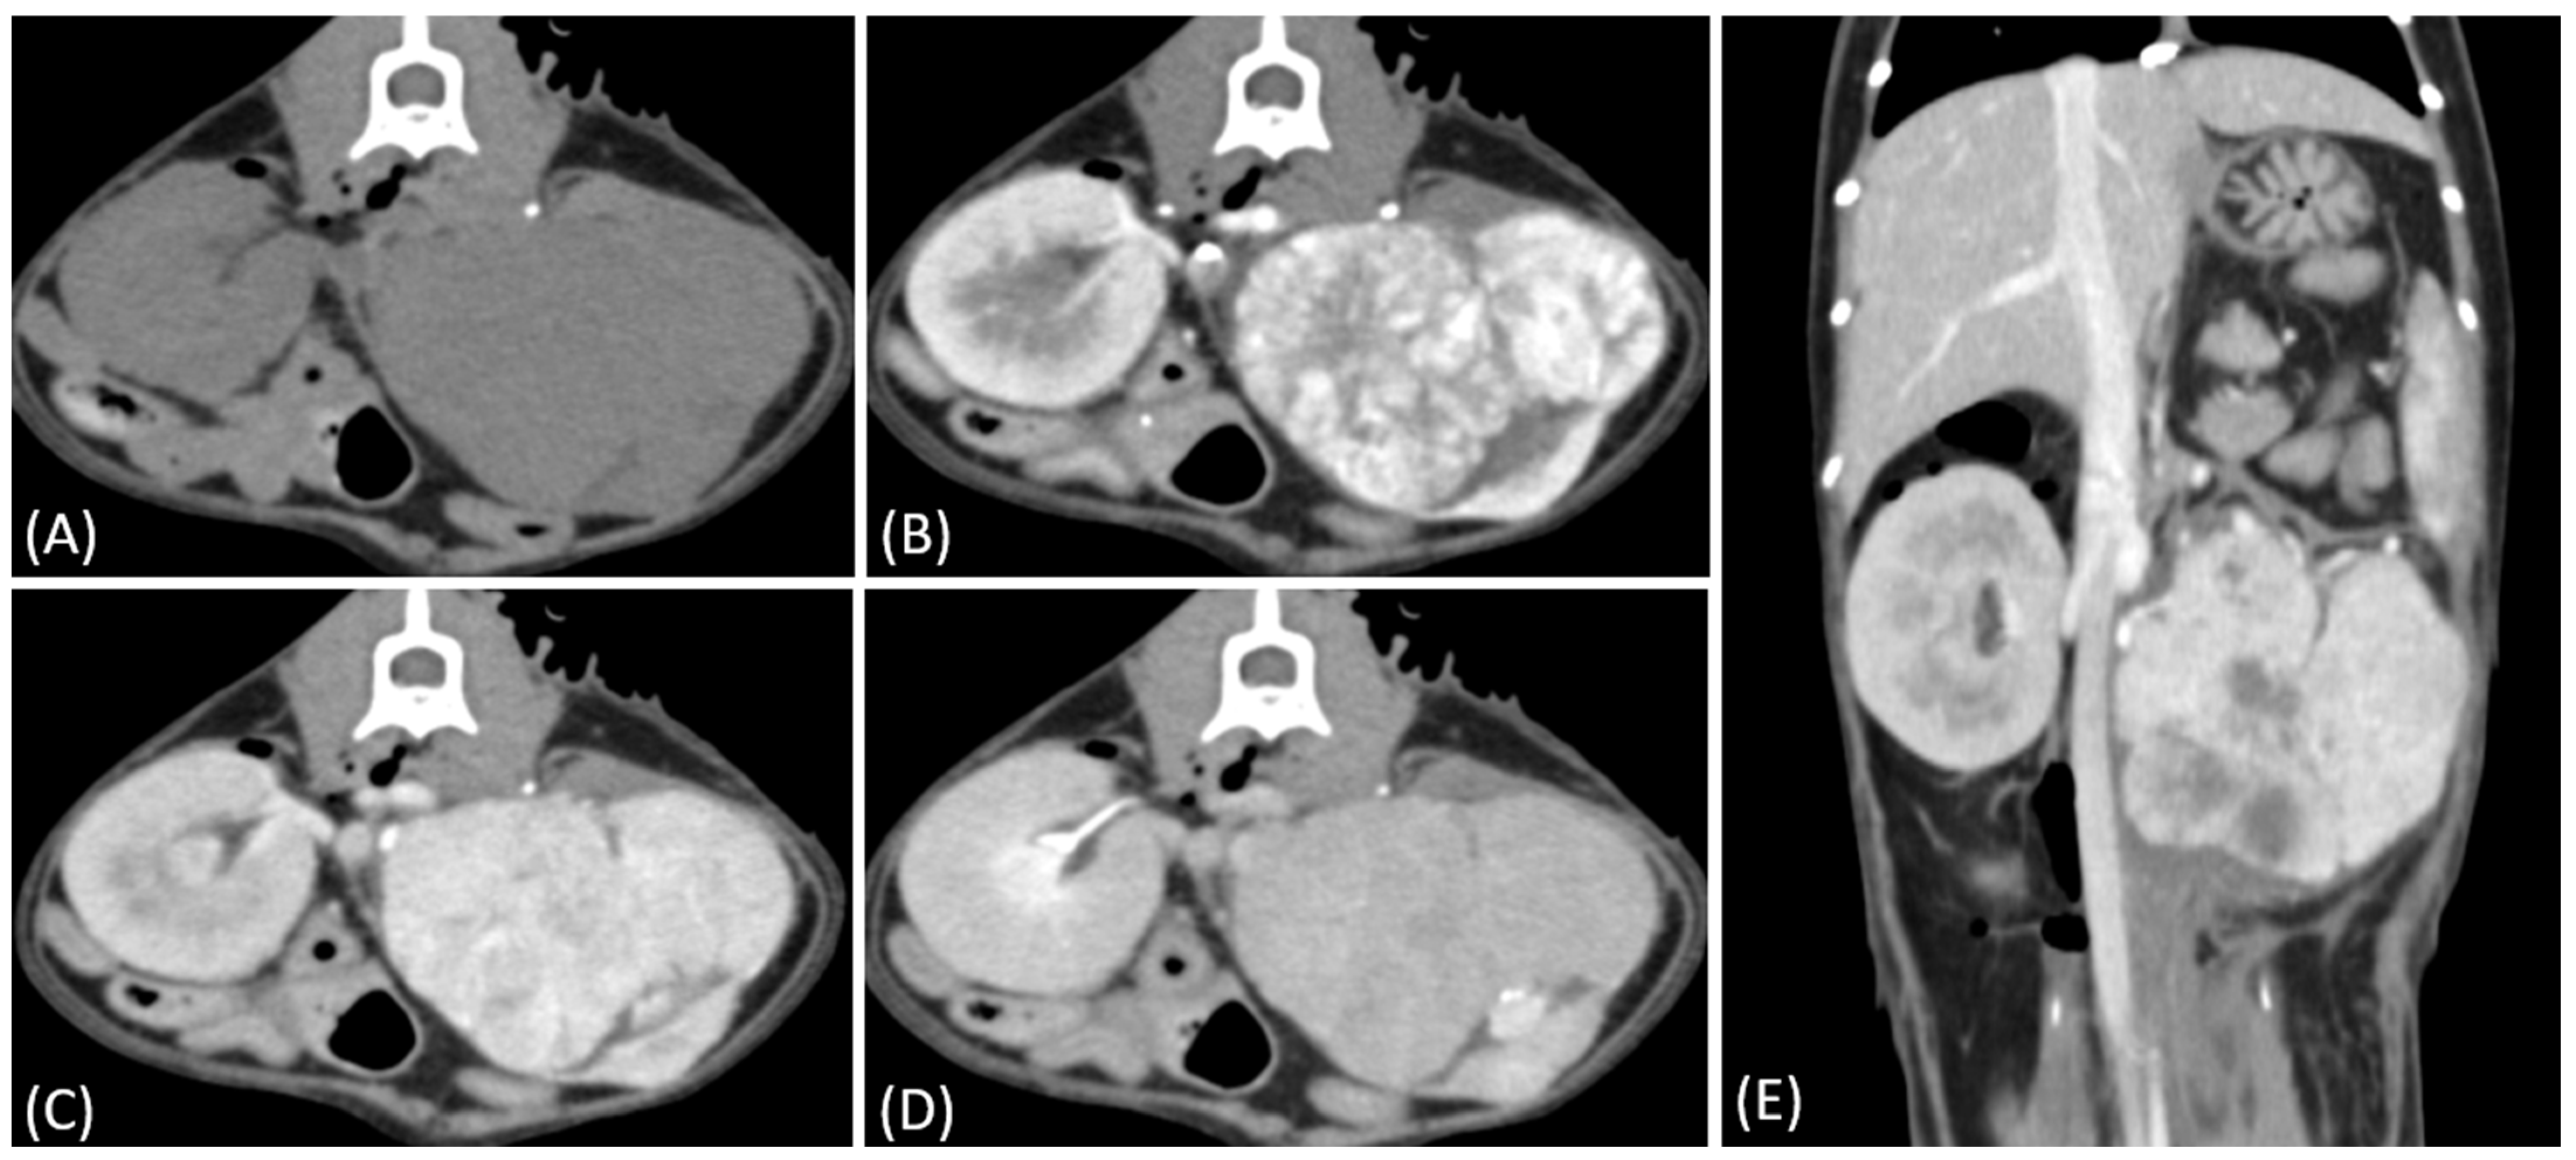

Figure 3.

(A) Pre-contrast, (B) corticomedullary phase, (C) nephrographic phase, and (D) delayed nephrographic/early excretory phase contrast-enhanced computed tomography (CT) images of a cat with bilateral renal and small intestinal lymphoma. The right kidney shows an infiltrative mass (black arrow), while the left kidney has an expansile mass (white arrow). Both tumors are homogeneous and hypodense, demonstrating progressive enhancement.